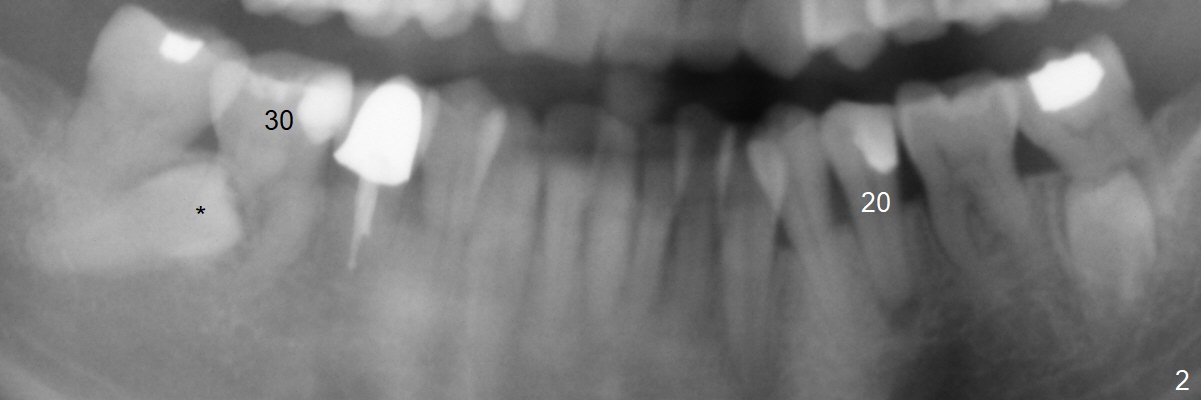

A 45-year-old woman with severe crowding (Fig.2) presented to my office 9 years ago; the tooth #18 appears to have root resorption, most likely due to a supernumerary tooth (Fig.1 *). The latter seems to be erupting in 6 and 9 years (Fig.2,3), probably because of immature apex (Fig.2, as compared to the supernumerary tooth in the lower right (*)). Recently the patient has transient sensitivity at #18. The tooth has mobility I without deep periodontal pockets. If the tooth #18 turns to be non-salvageable, what should be done? The tooth #20 has received root canal therapy, while the tooth #29 has had RCT retreat.